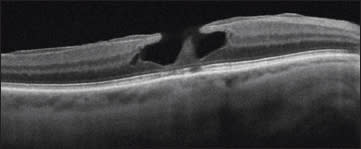

A true lamellar macular hole has a partial-thickness defect with surrounding overhanging borders over the floor of the LMH (Figure 2). Gaudric has also emphasized the presence of split foveal edges at the margin of the LMH on OCT.9 While ERM is often present, it is not a prominent part of LMH.

Figure 2. A true lamellar macular hole has a partial-thickness defect with surrounding overhanging borders over its floor.